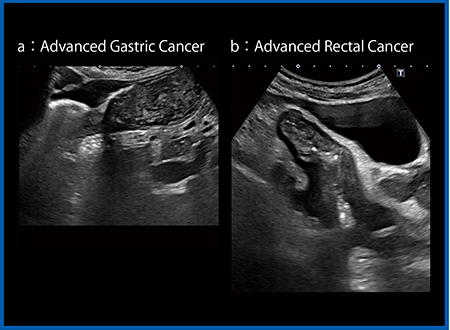

ApliPure plusとPrecision Imagingの適用は消化管の検査には最適である。図8 aは進行胃がんであるが,前庭部に胃の内容物が貯留し,そこに胃排出を低下させる病変がある。ApliPure plus 2とPrecision 2によりスペックルを除去することで粘膜下層のつながりをしっかりと把握でき,病変部の層構造の消失が認められる。図8 bは直腸がんであるが,層構造の消失した限局性の肥厚と近傍のリンパ節腫大が認められる。ApliPure plus 2とPrecision 2により,従来と比較して画像が非常に明瞭となっている。

図8 ApliPure plusとPrecision Imagingによる進行胃がん(a)

および直腸がん(b)の描出